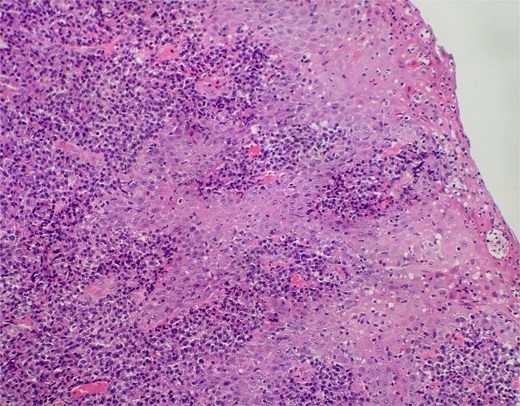

On clinical examination, harsh stridor with increased work of breathing was noted. Flexible nasoendoscopy demonstrated generalized supraglottic oedema with impending upper airway obstruction. Intravenous dexamethasone was commenced. A surgical tracheostomy with laryngeal biopsies under general anaesthetic was carried out. Histological examination (Figs 1 and 2) demonstrated hyperplastic, hyperkeratotic squamous mucosa with reactive atypia and an underlying dense polyclonal plasmocytic inflammatory infiltrate. No granulomata, prominent eosinophils, or stigmata of vasculitis were seen. Connective tissue disease screening demonstrated normal antinuclear antibody levels with positive perinuclear anti-neutrophil cytoplasmic antibodies. Anti-proteinase 3 levels returned as 3.7 IU/ml (range 0–1.9), while antimyeloperoxidase levels were normal. Rheumatology was consulted, and a provisional diagnosis of PCM was made. Serial laryngoscopy demonstrated resolution of the oedema, with the supraglottis regaining a normal appearance despite gradual tapering of the intravenous dexamethasone. A tracheostomy capping trial was successful. The patient was decannulated uneventfully and discharged on oral prednisolone. Three months later, he was maintained on 5 mg prednisolone—attempts to taper any further caused symptoms recurrence. Outpatient referral was made to Rheumatology for medical management with steroid-sparing therapy. Unfortunately, the patient was lost to follow-up due to failure to attend for outpatient review.

Slide from index presentation under higher magnification again demonstrating plasmocytic infiltration.